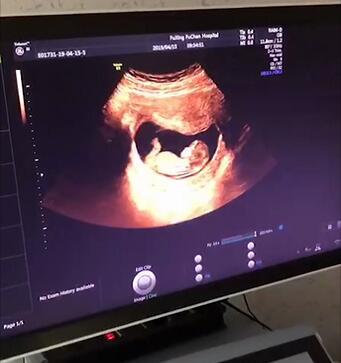

四、四维彩超

佛山都市妇产医院温馨提示:做四维彩超的最佳时间为怀孕22-26周,因为这个时段胎儿的肢体及各主要脏器已经全部发育,而且羊水较适合做胎儿畸形筛查。

检查项目包括:观察胎儿鼻唇部、心脏,可发现大部分解剖异常和出生缺陷,如无脑儿、脑积水、脊柱裂、肢体畸形、严重唇腭裂、先天性心脏病等。